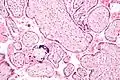

![]() Micrografía de citomegalovirus (CMV) infección de la placenta (placentitis CMV), una infección de transmisión vertical: El característico gran núcleo de una célula infectada con CMV se ve descentrada en la parte inferior derecha de la imagen, tinción H&E. | ||

Además de infectar al feto, los patógenos transplacentarios pueden causar placentitis (inflamación de la placenta) y/o corioamnionitis (inflamación de las membranas fetales).

Placentitis por citomegalovirus (CMV)